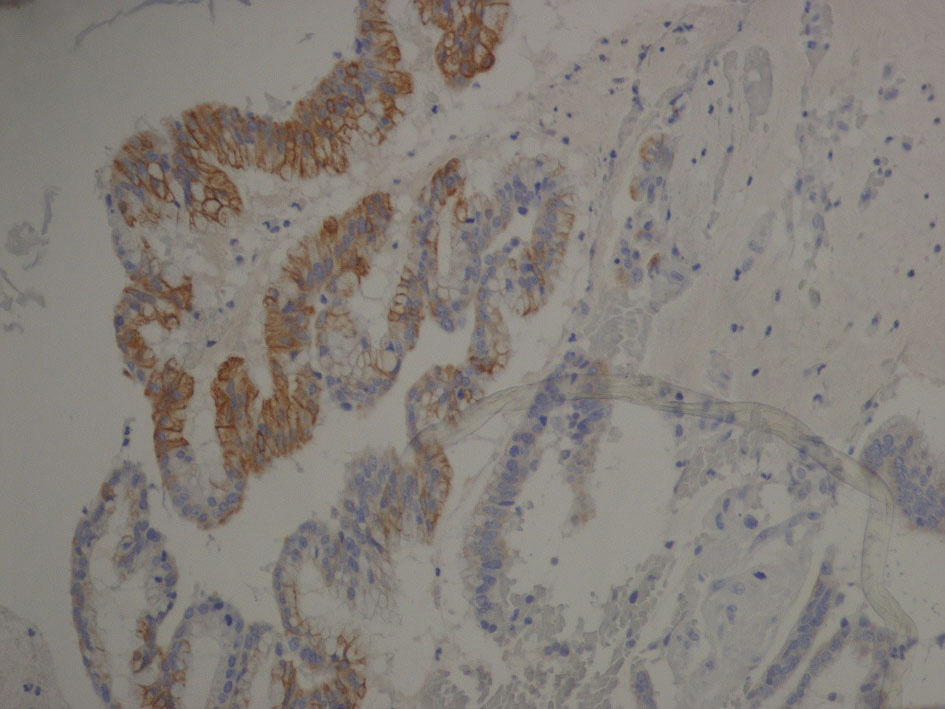

Immunophenotype was: cytocheratine 20+, CDX2a+, cytocheratine 7-, WT1-, negative estrogen and progesteron receptors; stromal and vascular invasion was observed (Fig. 6, 7).

![]() Click for large image | Figure 6. Immunophenotype image: cytocheratine 20+ (brown color). Cytocheratine 20 is expressed by mature enterocytes and goblet cells and is specifically found in the gastric and intestinal mucosa. |